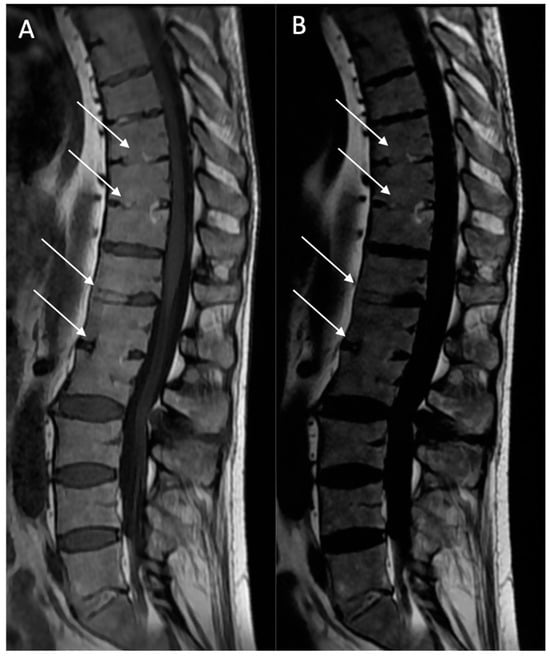

Fatty lesion (BMF): Defined as the presence of high signal intensity, similar to that of adipose tissue, on T1w MR images, or persistent fat areas on the “fat-only” Dixon FST images (Figure 2).

Figure 2. Multiple fatty lesion (BMF) changes and sacroiliac structural changes with partial ankylosis in a 44-year-old patient. A T1w sagittal sequence showing BMF localization at a longitudinal ligamentary structure enthesis (arrows) (A). A T2w Dixon (fat) image more clearly showing BMF localization (arrows). No ankylosis, sclerosis, or erosions were found (B). A T1w coronal oblique sequence of a sacroiliac joint showing periarticular fatty changes (*). A T1w coronal oblique sequence on a sacroiliac joint showing structural changes with partial ankylosis (arrrowheads). No inflammatory changes were noted (C,D).